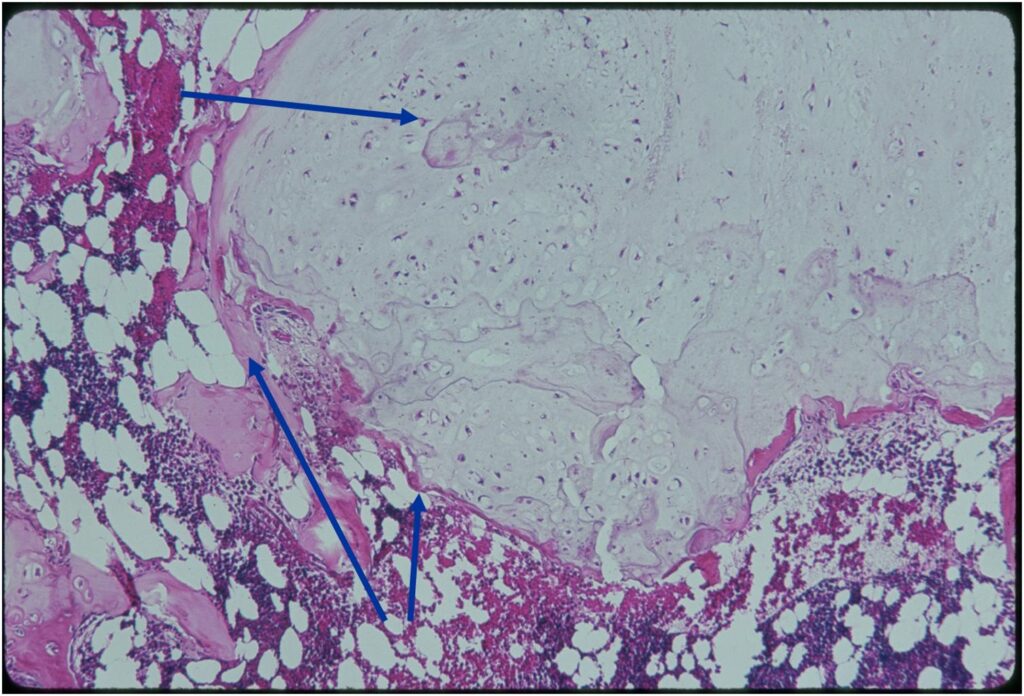

Microscopic Pathology

- Enchondromas are well defined lesions with cartilage arranged in lobules that are separated by fibrovascular septa

- Enchondral ossification may occur around periphery of lobules and when calcified appear as “Rings and Arcs” on X-rays

- Cells are in lacunae and have small dark nuclei

- Low cell count, cells appear bland with few chondrocytes and are similar size and shape

- Although some enchondromas may have areas that are hypercellular and may have two or three cells within a lacunae

- No entrapment or destruction of trabeculae

- Rests of hyaline cartilage with a lobular growth pattern

- Cells are within lacunae

- Hypocellular with cells spaced apart separated by matrix

- Cells have small nuclei and are similar size and shape (no pleomorphism)

- No mitotic figures

- The matrix has a ground glass basophilic appearance

- The matrix contains glycosaminoglycans that attract fluid/water and gives it a bsophilic appearance and show as high signal intensity on T2 weighted MRI

- The collagen of the matrix is organized in a manner such that the refractile index under a microscope gives a ground glass appearance to the matrix. One can not visualize the actual collagen fibers.